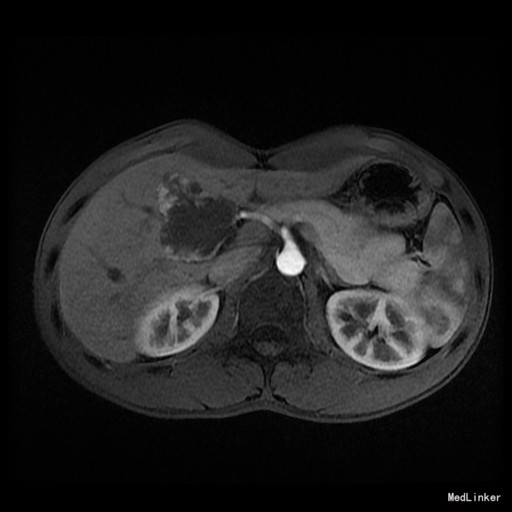

查体:腹平,未见曲张静脉、色素沉着,无局部隆起或凹陷,未见胃肠型,腹软,全腹部无压痛、反跳痛。 辅查:上腹部MRI(我院 2015-09-13):肝S4/5段血管瘤(1枚)。

诊断:肝血管瘤 治疗:完善相关检查,排除手术禁忌证于2015-09-18行肝S4/5段血管瘤切除+胆囊切除术,术后恢复良好,现一般情况好。

随访:(肝S4/5段血管瘤)海绵状血管瘤;周围肝组织小叶结构保存,肝细胞胞浆内见较多胆色素颗粒;“切缘”未见肿瘤。 讨论:肝海绵状血管瘤是肝脏最常见的良性肿瘤,约占肝脏良性肿瘤的84%,一般无临床症状,常为体检中发现。海绵状血管瘤内的血窦和血窦内缓慢流动的血液形成MRI颇具特征性表现,T2WI呈均匀高信号,随着回波时间延长,信号强度增高,临床上称为灯泡征。增强扫描呈“快进慢出”表现,即动脉期边缘结节样明显强化,门脉期及静脉期强化逐渐向中央扩展。影像学表现较具特征性,诊断不难。